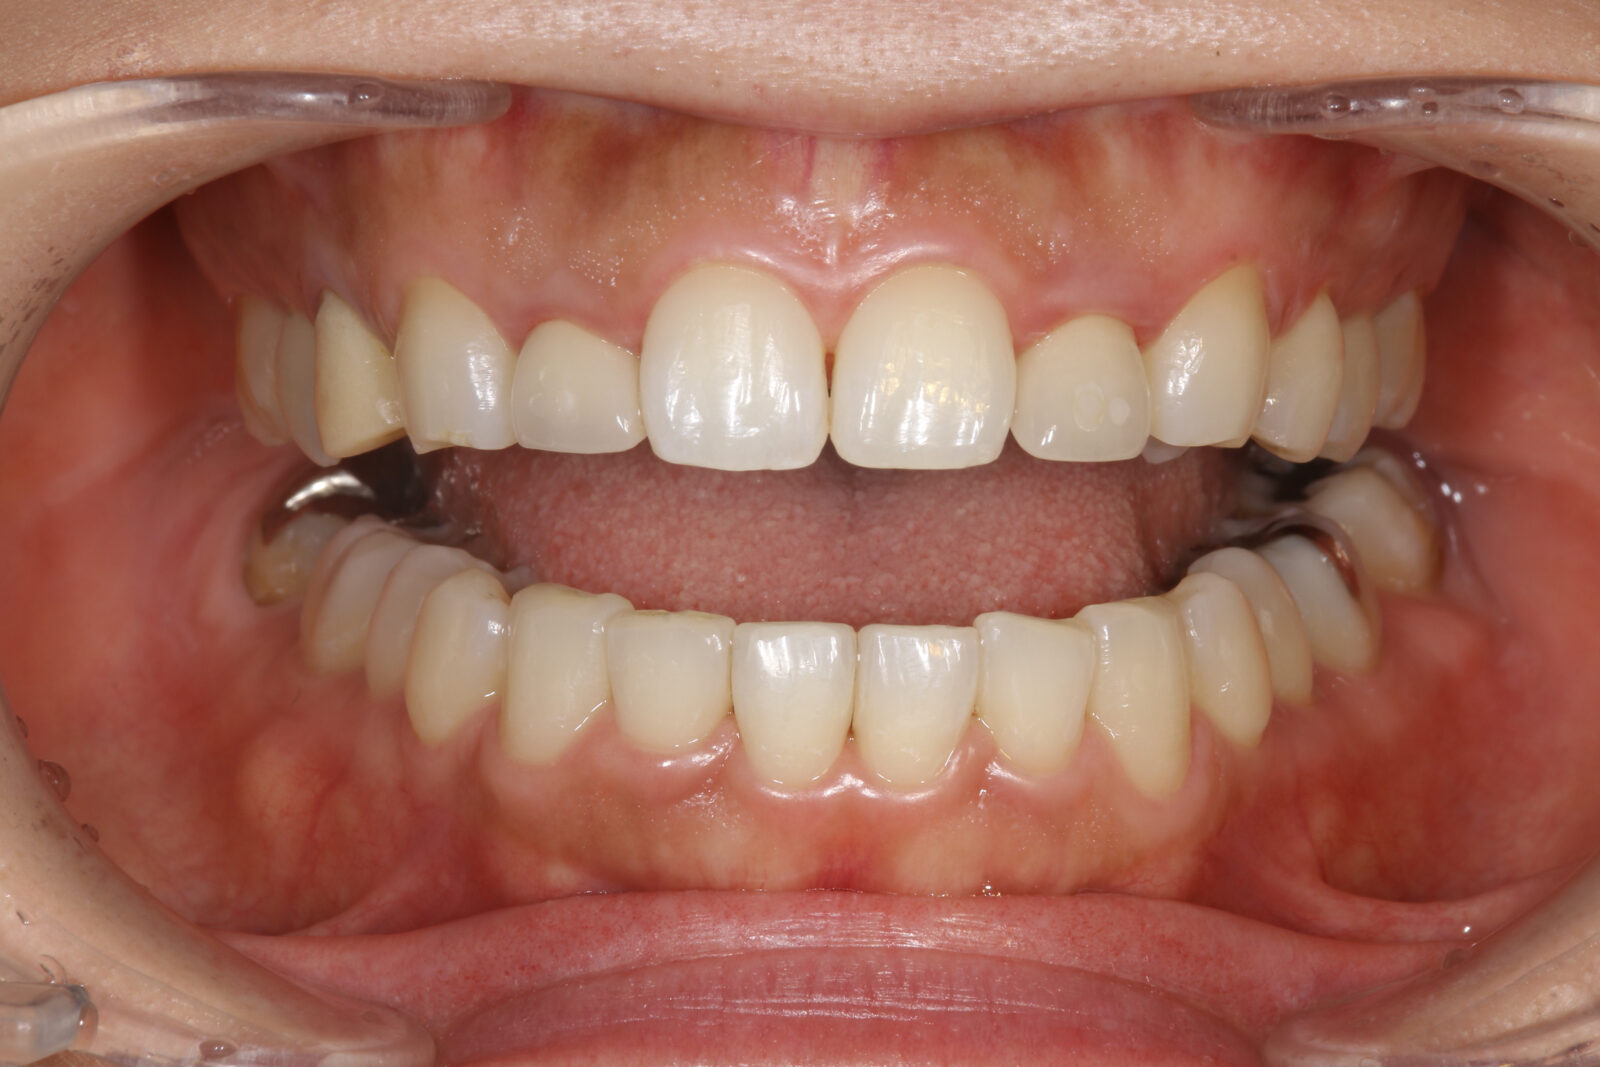

矯正治療を行なったにも関わらず、上顎左右側の側切歯の歯肉ラインが揃っていません。

上顎左右側の側切歯の補綴装置が矯正治療以前のままです。

- 他の歯科医院にて矯正治療を施術されたが、見た目が良くない・歯肉レベルが揃ってないとのことで治療を希望された。知り合いに当医院を勧められ来院した。

- 歯周外科の後、上顎前歯3本のラミネートベニア、4本のオールセラミッククラウンを装着した。

審美的な仕上がりで、患者自身も満足した。6年経過し良好である。